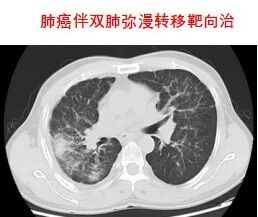

3.分子靶向治疗

靶向治疗,是在细胞分子水平,针对已经明确的致癌位点(该位点可以是肿瘤细胞内部的一个蛋白分子,也可以是一个基因片段的突变)进行靶向抗肿瘤治疗。分子靶向治疗具有特异性抗肿瘤作用,使肿瘤细胞特异性死亡,不会波及肿瘤周围的正常组织,其疗效增加,毒副作用明显减少。